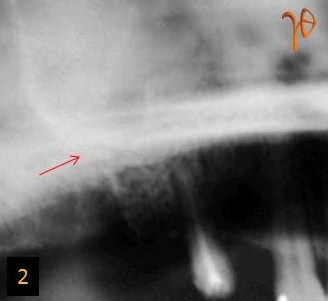

Μετεξακτική λοίμωξη(Εικ.1) μετά από εξαγωγή του #17, μη ανταποκρινόμενη στη συντηρητική αγωγή. Μετά από πανοραμική ακτινογραφία(Εικ.2) και καλλιέργεια, θετική για Β-στρεπτόκκοκκο(ομάδα C κατά Lancefield), έγινε τοπική απόξεση και συρραφή με την ενδεικνυόμενη αντιβιοτική κάλυψη. Η λοίμωξη δεν υποχώρησε και με την υπολογιστική τομογραφία(Εικ.3 και 4) επιβεβαιώθηκε η κλινική υποψία στοματοκολπκής επικοινωνίας και οδοντογενούς ιγμορείτιδας.

Εικ. 1: Μετεξακτική λοίμωξη στην άνω δεξιά γομφιακή περιοχή (βέλος).